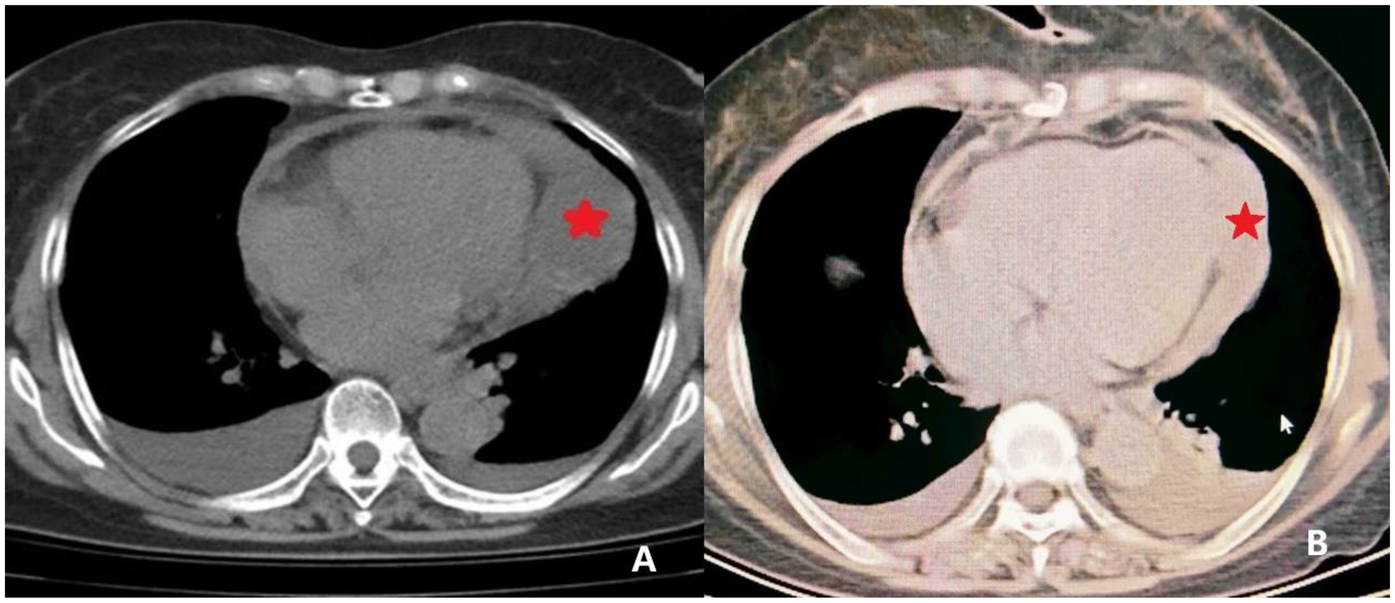

A 69-year-old woman presented with a 15-day history of chest tightness of unclear origin, which improved with rest but was accompanied by reduced activity tolerance. Chest CT (Figure 1) indicated localized thickening of the pericardium with a fluid-density shadow and a soft tissue-density lesion at the cardiac apex. Cardiac ultrasound (Figure 2) revealed left atrial enlargement and an echogenic mass (∼69 mm × 50 mm) in the pericardial cavity outside the anterior left ventricular wall. The lesion had relatively clear margins and was associated with slightly impaired ventricular wall motion, suggesting an extracardiac mass.

Figure 1

CT imaging of the pericardial mass. (A) Preoperative CT image revealing localized pericardial thickening with associated areas of fluid density. A focal soft tissue density is noted at the cardiac apex (indicated by *) concerning for a space-occupying lesion. (B) Postoperative CT image demonstrating resolution of the pericardial thickening and absence of the previously noted soft tissue density at the cardiac apex, indicating successful resection.